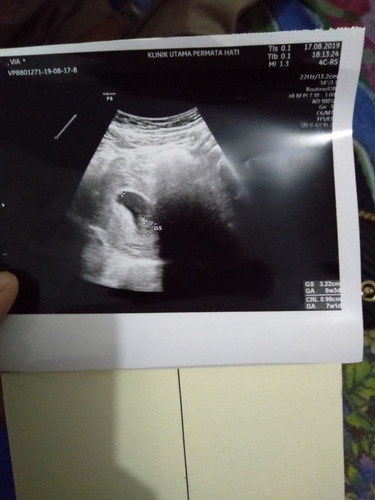

Bun mau tnya tdi usg terus dihasil usg nya panjang janinnya baru 0.99 kta dokternya kecil banget ktnya harus sering minum air teus minggu depan disuruh kontrol lagi usia kandunganku 7 minggu klw berdasarkan usg klw bidan 8 minggu, jdi galau bunn